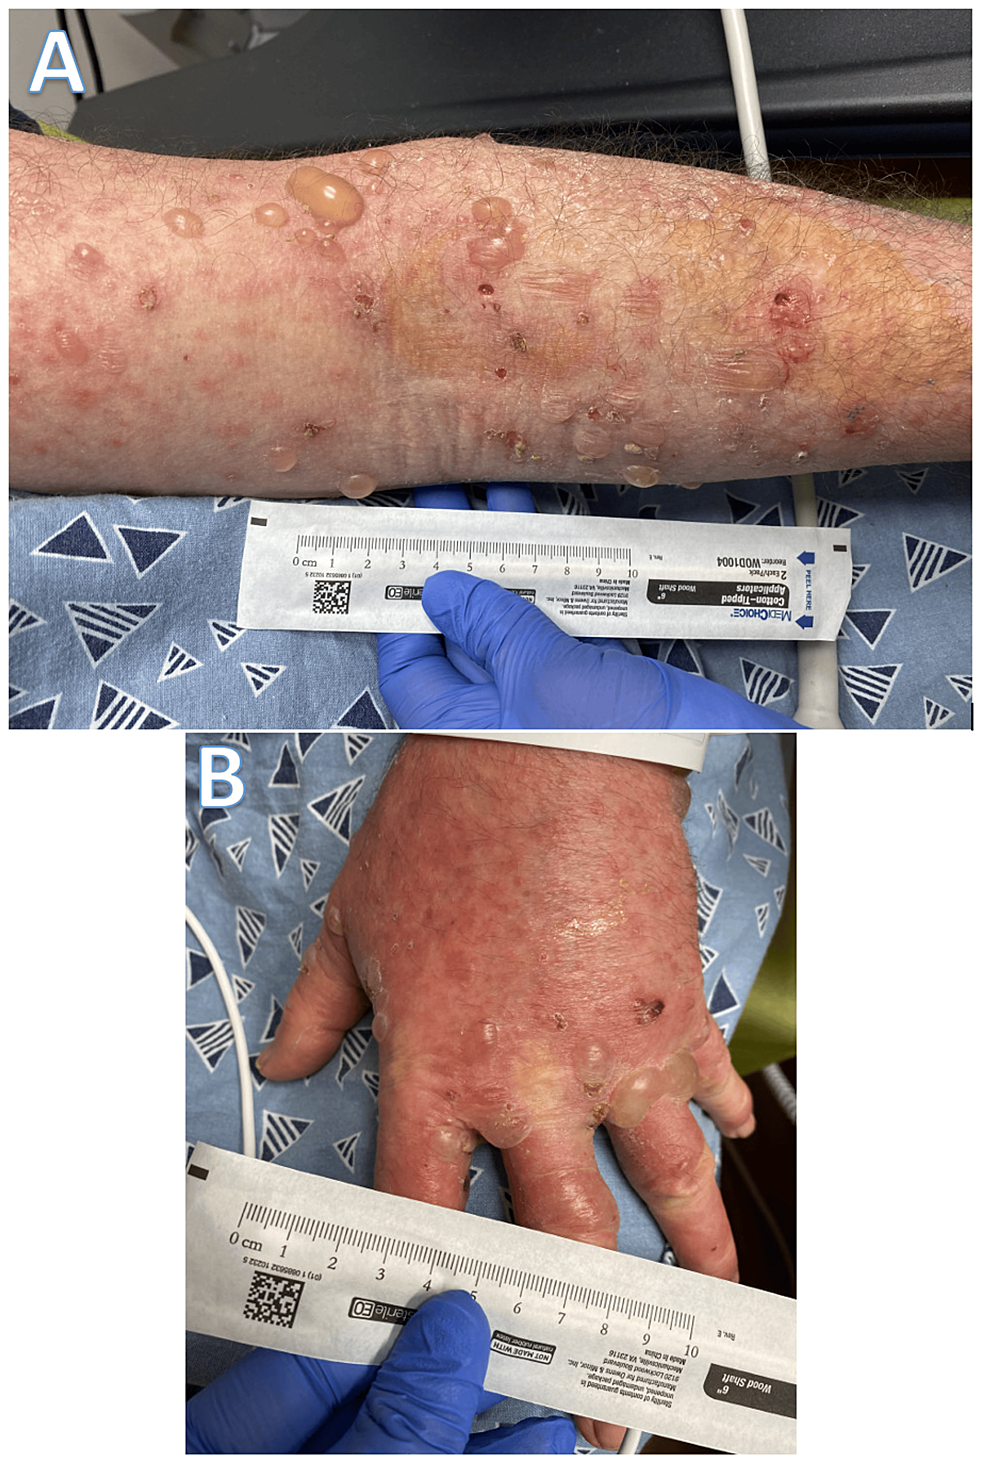

Wells Syndrome with Bullous Lesions - The Journal of Allergy and Clinical Immunology: In Practice

image size: 1577x1183

Wells Syndrome with Bullous Lesions - The Journal of Allergy and Clinical Immunology: In Practice

image size: 1577x1183